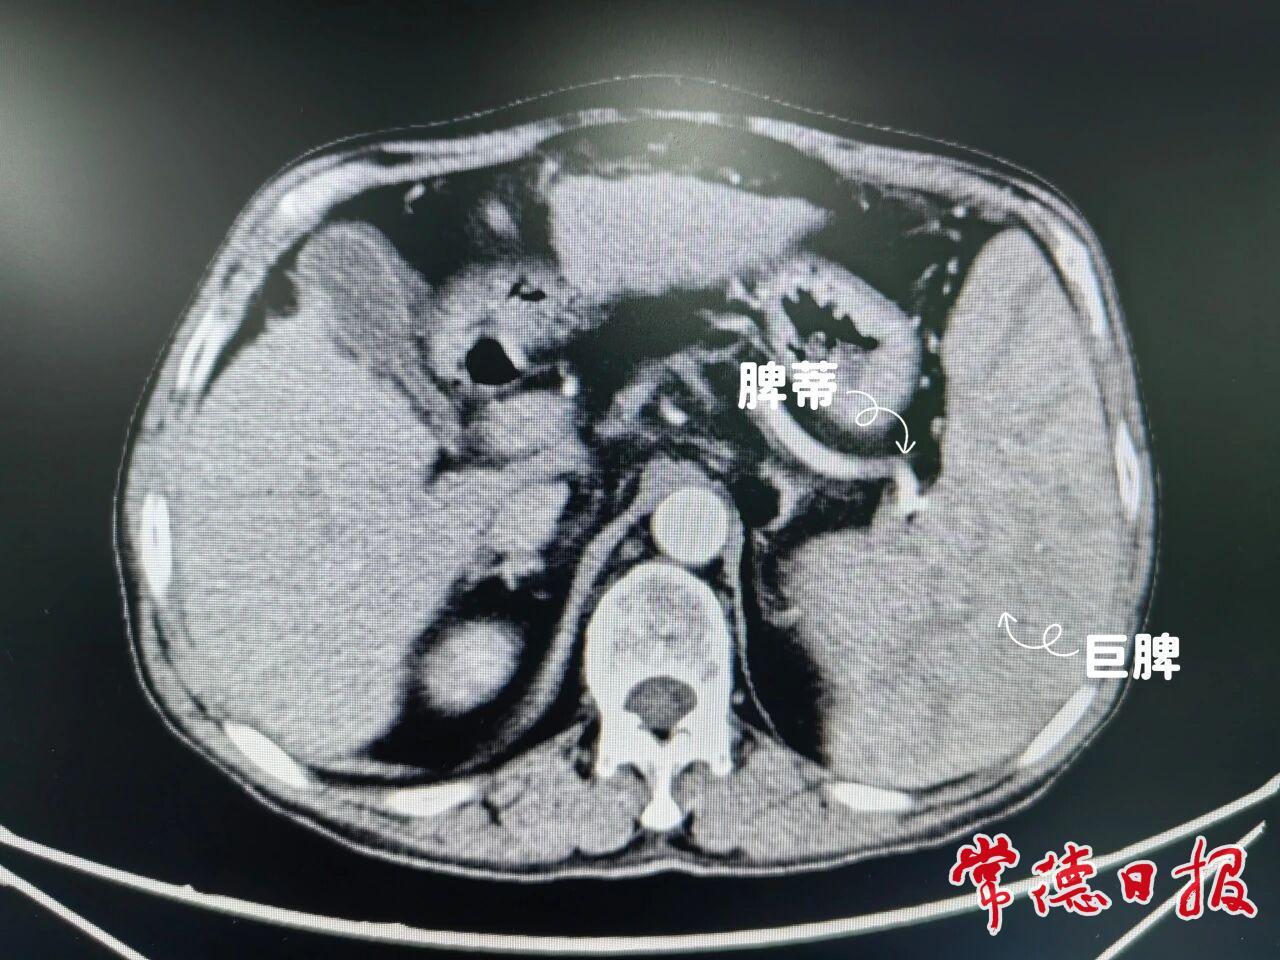

患者萬先生因早年血吸蟲感染導致肝硬化失代償,繼而引發門靜脈高壓、脾臟顯著腫大及脾功能亢進。長期病痛使他飽受貧血、腹水、嘔血等癥狀困擾,生活質量嚴重下降。由于腫大的脾臟持續破壞血細胞,進一步加劇了出血和感染風險,手術切除成為阻斷這一惡性循環的關鍵。

手術過程中,團隊精細操作,先精準阻斷脾動脈以減少血供,隨后逐步分離粘連組織和韌帶,完整游離脾臟,最后使用切割閉合器一次性處理脾蒂血管,將病變脾臟成功切除。歷經3個多小時,手術順利完成,術中出血量控制良好。